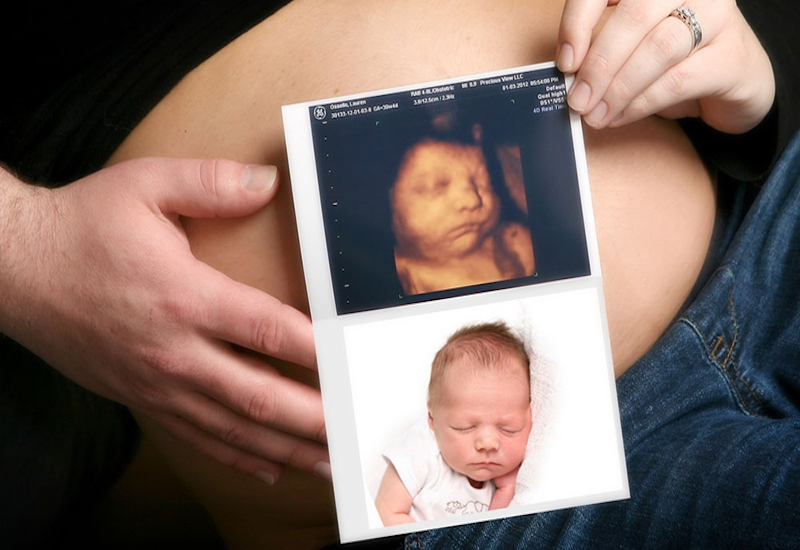

Siêu âm là một bước quan trọng trong vấn đề chăm sóc sức khỏe hiện đại, đặc biệt là trong thai kỳ, qua đó giúp cung cấp những hình ảnh có giá trị về sức khỏe của cả mẹ và thai nhi.

Với những tiến bộ của khoa học và công nghệ, các phương pháp siêu âm hiện nay đã phát triển đáng kể, bao gồm nhiều loại hình như quét 2D, 3D và 4D. Mỗi loại đều có những ưu điểm riêng biệt, chất lượng hình ảnh khác nhau và chi phí liên quan. Việc lựa chọn hình thức siêu âm nào sẽ phụ thuộc vào một số yếu tố và bác sĩ sẽ có chỉ định phù hợp nhất dựa trên tình trạng cụ thể của từng người.

Loại hình siêu âm ba chiều này mang lại hình ảnh chi tiết và chân thực hơn về thai nhi trong bụng mẹ.

Siêu âm 4D

Dựa trên công nghệ 3D, siêu âm 4D cho phép ghi lại chuyển động của thai nhi rõ ràng, chi tiết. Siêu âm 4D giúp cha mẹ có thể tận mắt chứng kiến những cử chỉ và biểu cảm đầu tiên của con mình. Đổi lại, chi phí siêu âm 4D sẽ tương đối cao.